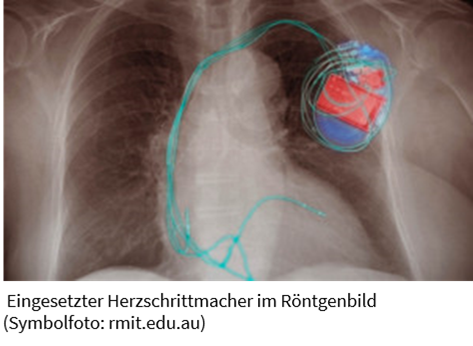

Melbourne (pte014/25.01.2021/11:30) – Ein neuartiger Generator von Forschern der RMIT University https://www.rmit.edu.au/ revolutioniert die Stromversorgung von tragbarer Elektronik und selbst von Herzschrittmachern. Das Gerät ist 100.000-mal dünner als ein menschliches Haar und achtmal effizienter. Es basiert auf dem piezoelektrischen Prinzip. Bestimmte Werkstoffe und Werkstoffkombinationen erzeugen elektrischen Strom, wenn sie unter Druck geraten.

Kombiniert mit einem kleinen Gewicht, das sich bewegt, wenn man geht, lässt sich so Strom erzeugen. Noch einfacher geht es mit einem Generator, der in Schuhe integriert wird. Bei jedem Schritt erzeugt er Strom, kombiniert mit einer winzigen Batterie ist sogar eine kontinuierliche Stromversorgung möglich. Soll er zur Stromversorgung eines Herzschrittmachers eingesetzt werden, reicht der wechselnde Blutdruck als mechanischer Antrieb aus.